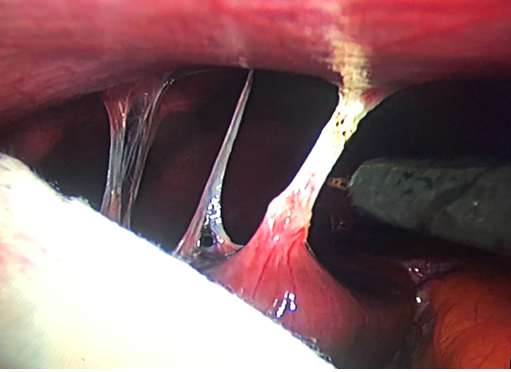

Hình ảnh các dây chằng giữa mặt trước gan và thành bụng qua nội soi

Vào ổ bụng qua 1 Trocart 10mm trên rốn, đưa camera vào quan sát thấy: Phần phụ phải kích thước to, thâm nhiễm, manh tràng phải dính vào vết mổ cũ, ít dịch rãnh đại tràng phải, có các dây chằng dính giữa mặt trước bao gan và thành bụng trước. Vào thêm 1 trocart 10mm ở hố chậu phải và 1 Trocart 5mm ở hố chậu trái

Tiến hành, gỡ dính, cắt các dây chằng bao gan, lau sạch ổ bụng. Sau mổ điều trị kháng sinh phối hợp (Metronidazol và Cefoperazole ABR). Hậu phẫu ổn định, các triệu chứng hết dần.